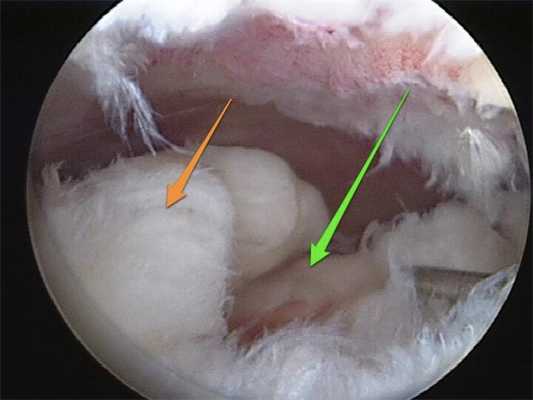

При повреждениях менисков используют несколько видов артроскопических техник:

- накладывание шва;

- пластика мениска;

- частичная резекция нестабильных фрагментов мениска;

- тотальная менискэктомия (полное удаление).

Сегодня врачи отдают предпочтение артроскопическому восстановлению мениска, поскольку оно дает лучшие клинические и рентгенологические результаты, чем частичная и полная менискэктомия. Целостность мениска восстанавливают путем наложения шва или с помощью пластики. Такая операция позволяет стабилизировать движения в суставе и добиться равномерного распределения осевой нагрузки на суставные поверхности бедра и голени. А это, в свою очередь, снижает риск последующего развития остеоартроза.

С другой стороны, при тяжелых повреждениях далеко не всегда удается восстановить целостность мениска. Поэтому врачам часто приходится выполнять частичную резекцию или полностью удалять его. Это дает менее благоприятные результаты.